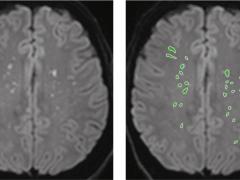

Licht traumatisch hoofd-hersenletsel bij kinderen

Detectie van cervicale wervelfracturen met AI